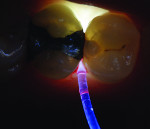

A recent development involves an innovative thin, flexible fiber-optic tip used for evaluating interproximal posterior caries (Microlux Proximal Caries Light Guide, AdDent, Inc., www.addent.com). This 0.75-mm thin light guide is also beneficial for visualizing root canal orifices within pulp chambers. For caries diagnosis, the thin light guide tip is slid into the gingival embrasure below the proximal contact under the marginal ridge. Figure 3 depicts a view from the occlusal. This method often shows caries with a higher definition than a conventional fiber-optic light guide.